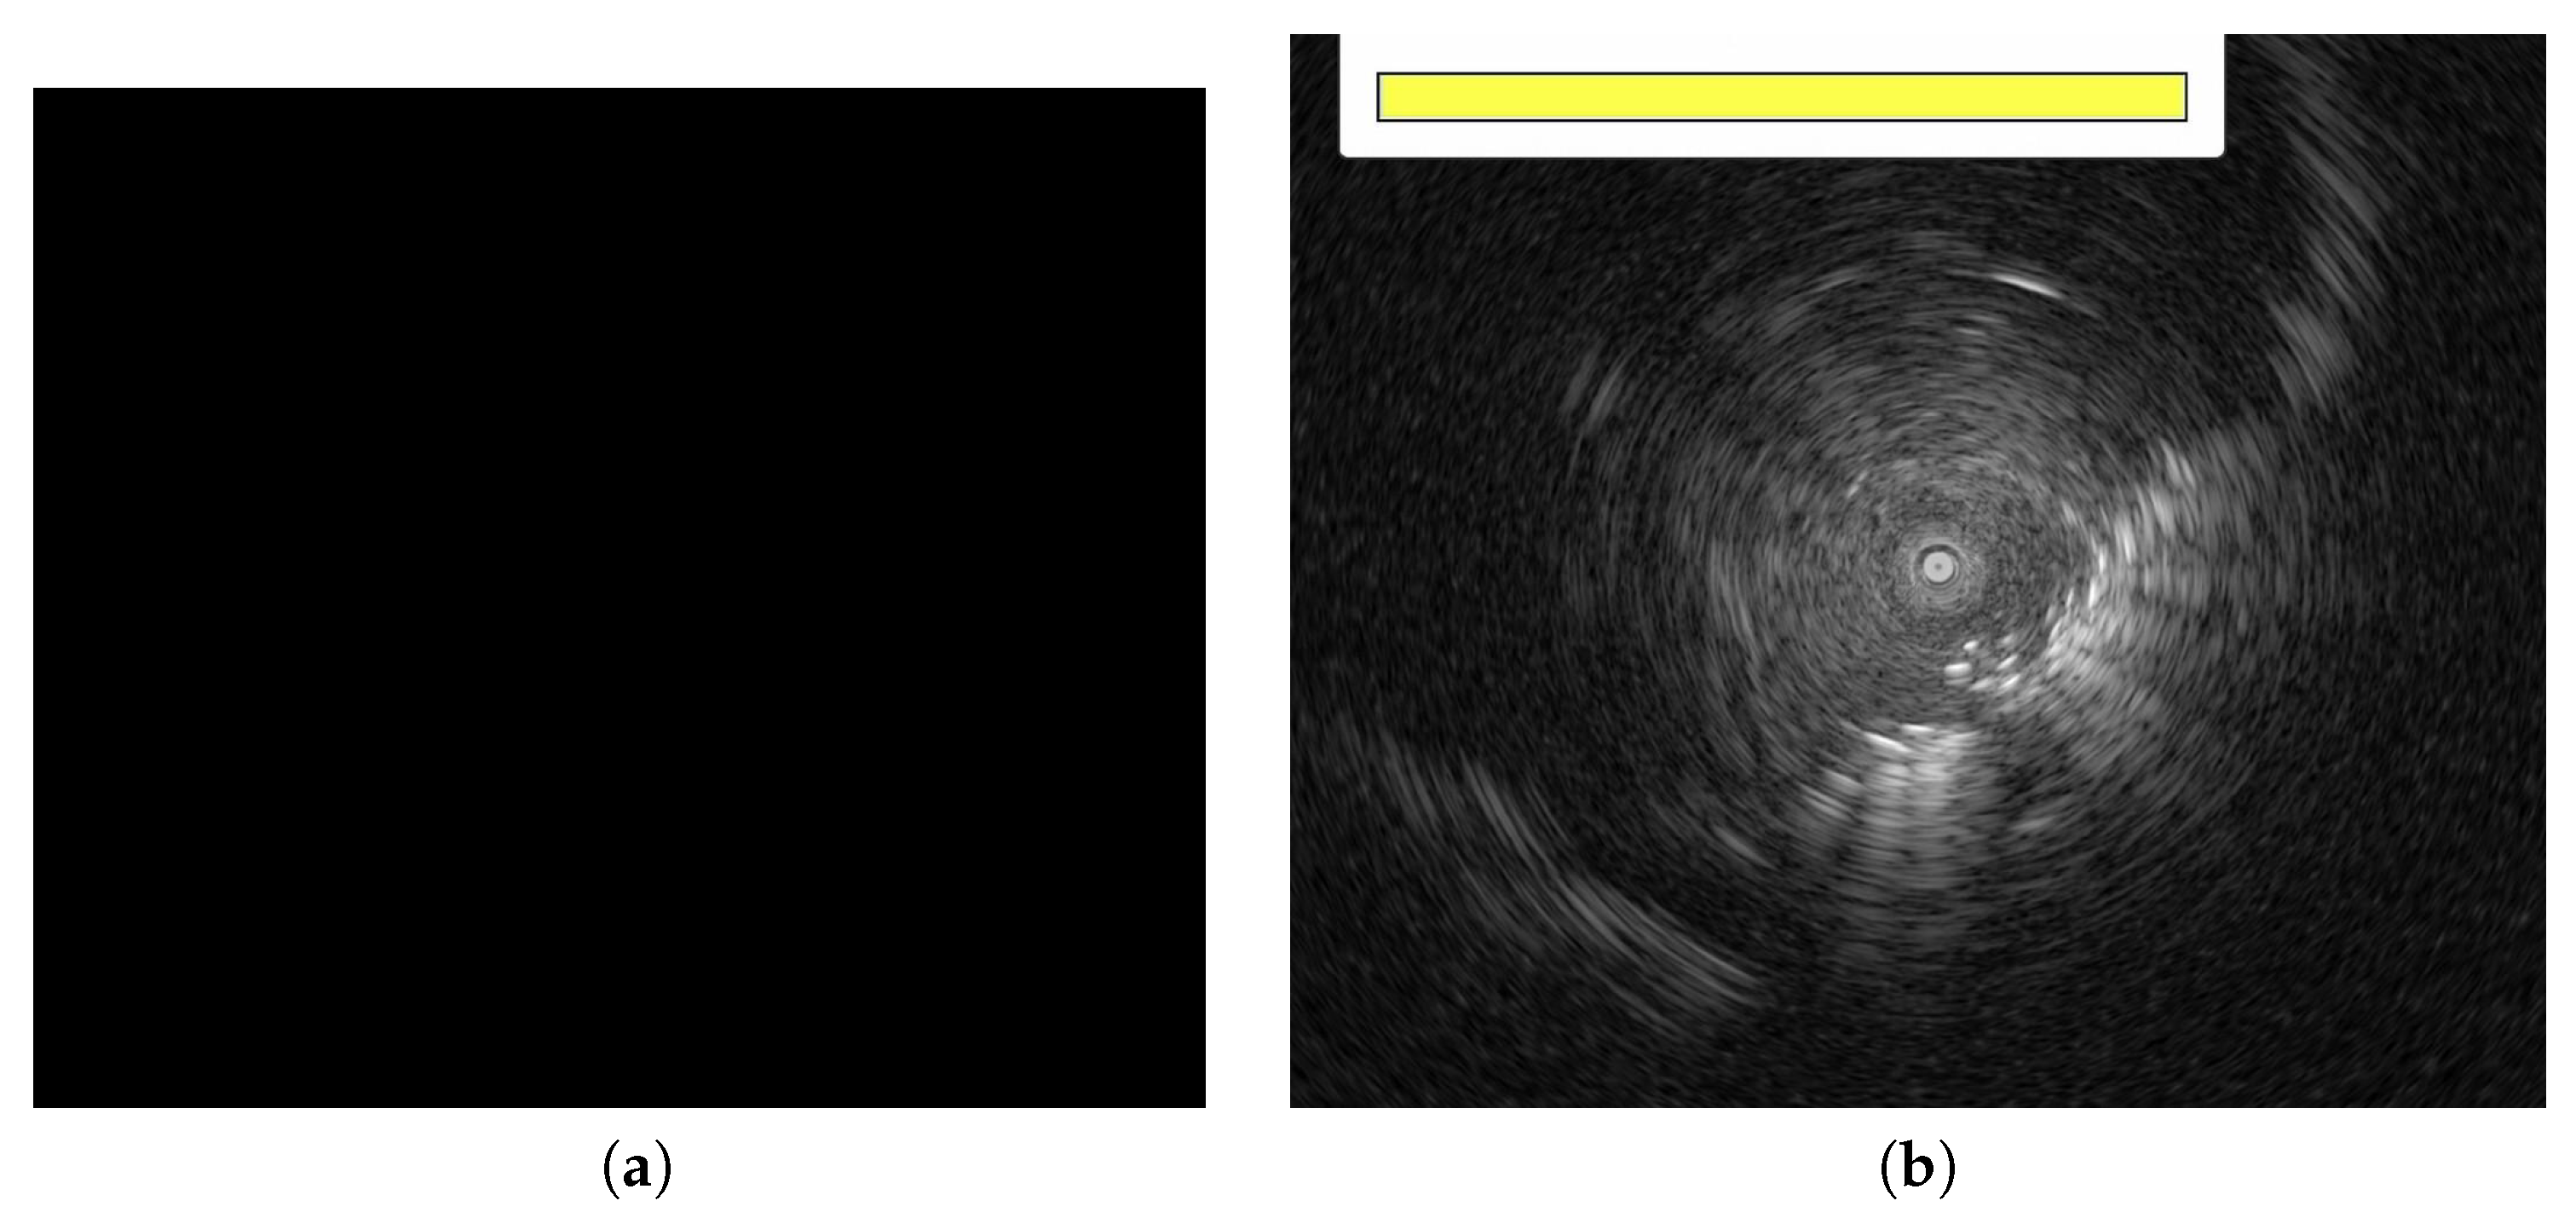

3.1. Data Pre-Processing